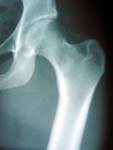

To diagnose osteoarthritis of the hip, a physician will take a thorough history and perform a thorough physical examination first. Following this, simple x-rays taken with the patient standing are an effective way to diagnose this condition.

Diagnostic tests

The simplest test to diagnose osteoarthritis of the hip is the x-ray. Taken with the patient standing up plain x-rays can diagnose the condition with great accuracy.

Osteoarthritis occurs when the joint surface cartilage (also called hyaline cartilage or articular cartilage) becomes worn away leaving the raw bone beneath exposed. The cartilage normally serves as a “pad” or a bearing in the joint. Under normal conditions, the cartilage bearing is slicker than a hockey puck on ice. When the bearing wears away, the result is a roughed joint surface that causes the pain and stiffness that people associate with osteoarthritis (See Figures 1-4).